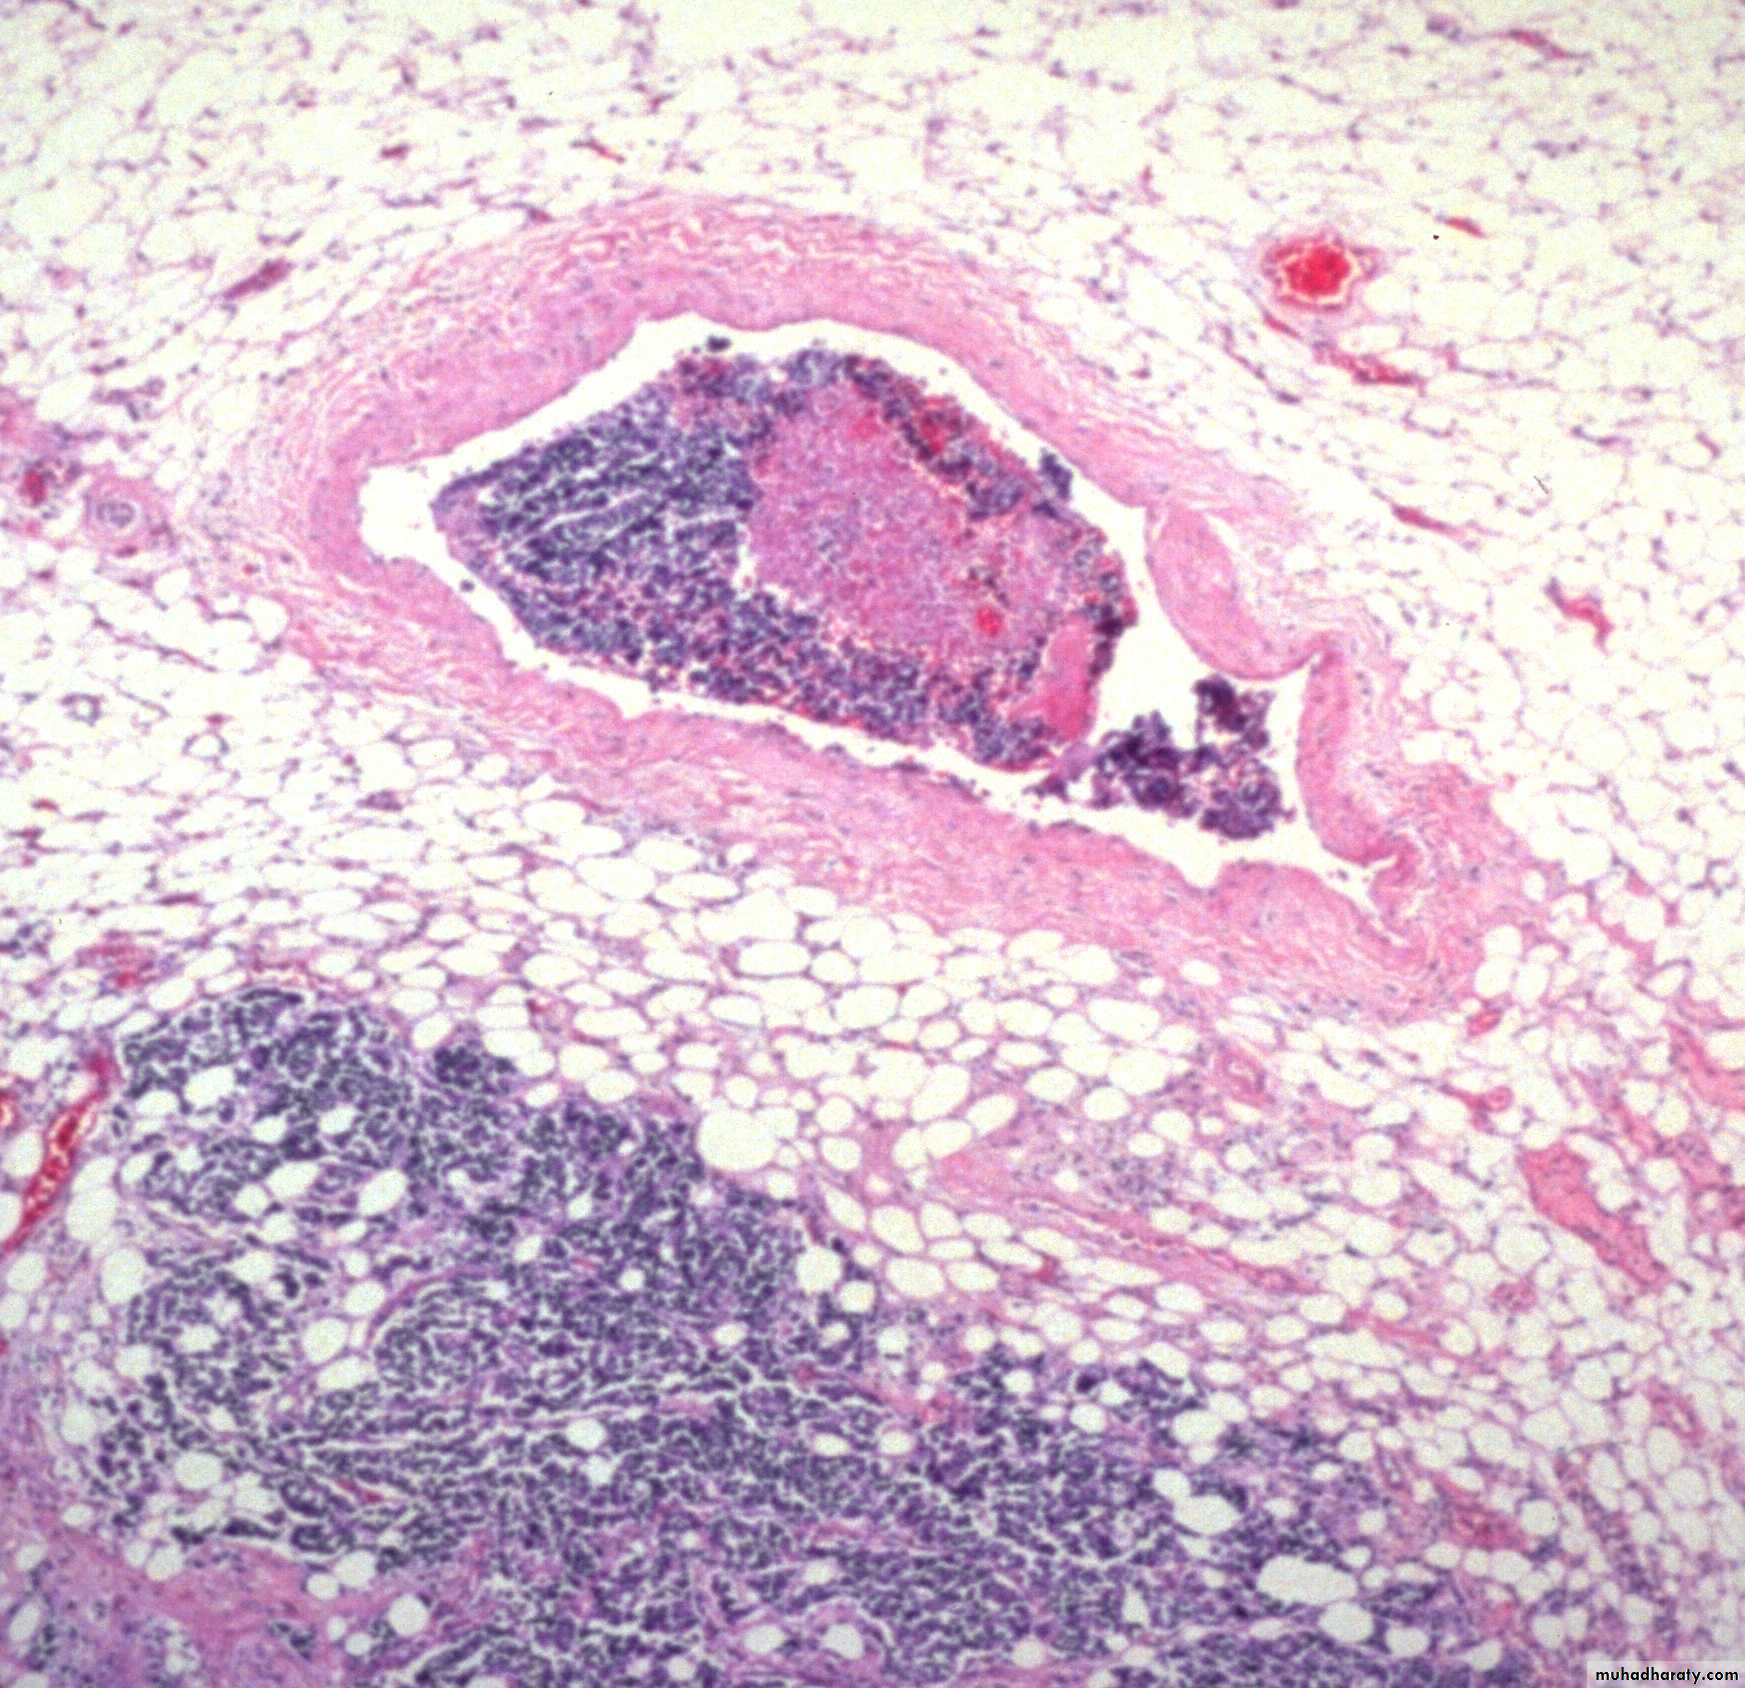

Blood (Haematogenous) Spread

Tumour cells are able to invade thin walled veins and grow along the venous system or embolize into the blood stream.

The site of initial metastasis (first-pass organ)

depends on the venous drainage of the location of the

tumour.

Lung , liver and brain are the main organs of hematogenous spread for cancers.

Blood spread is main way for Sarcoma and later for carcinoma